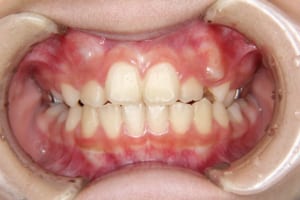

Before

治療前